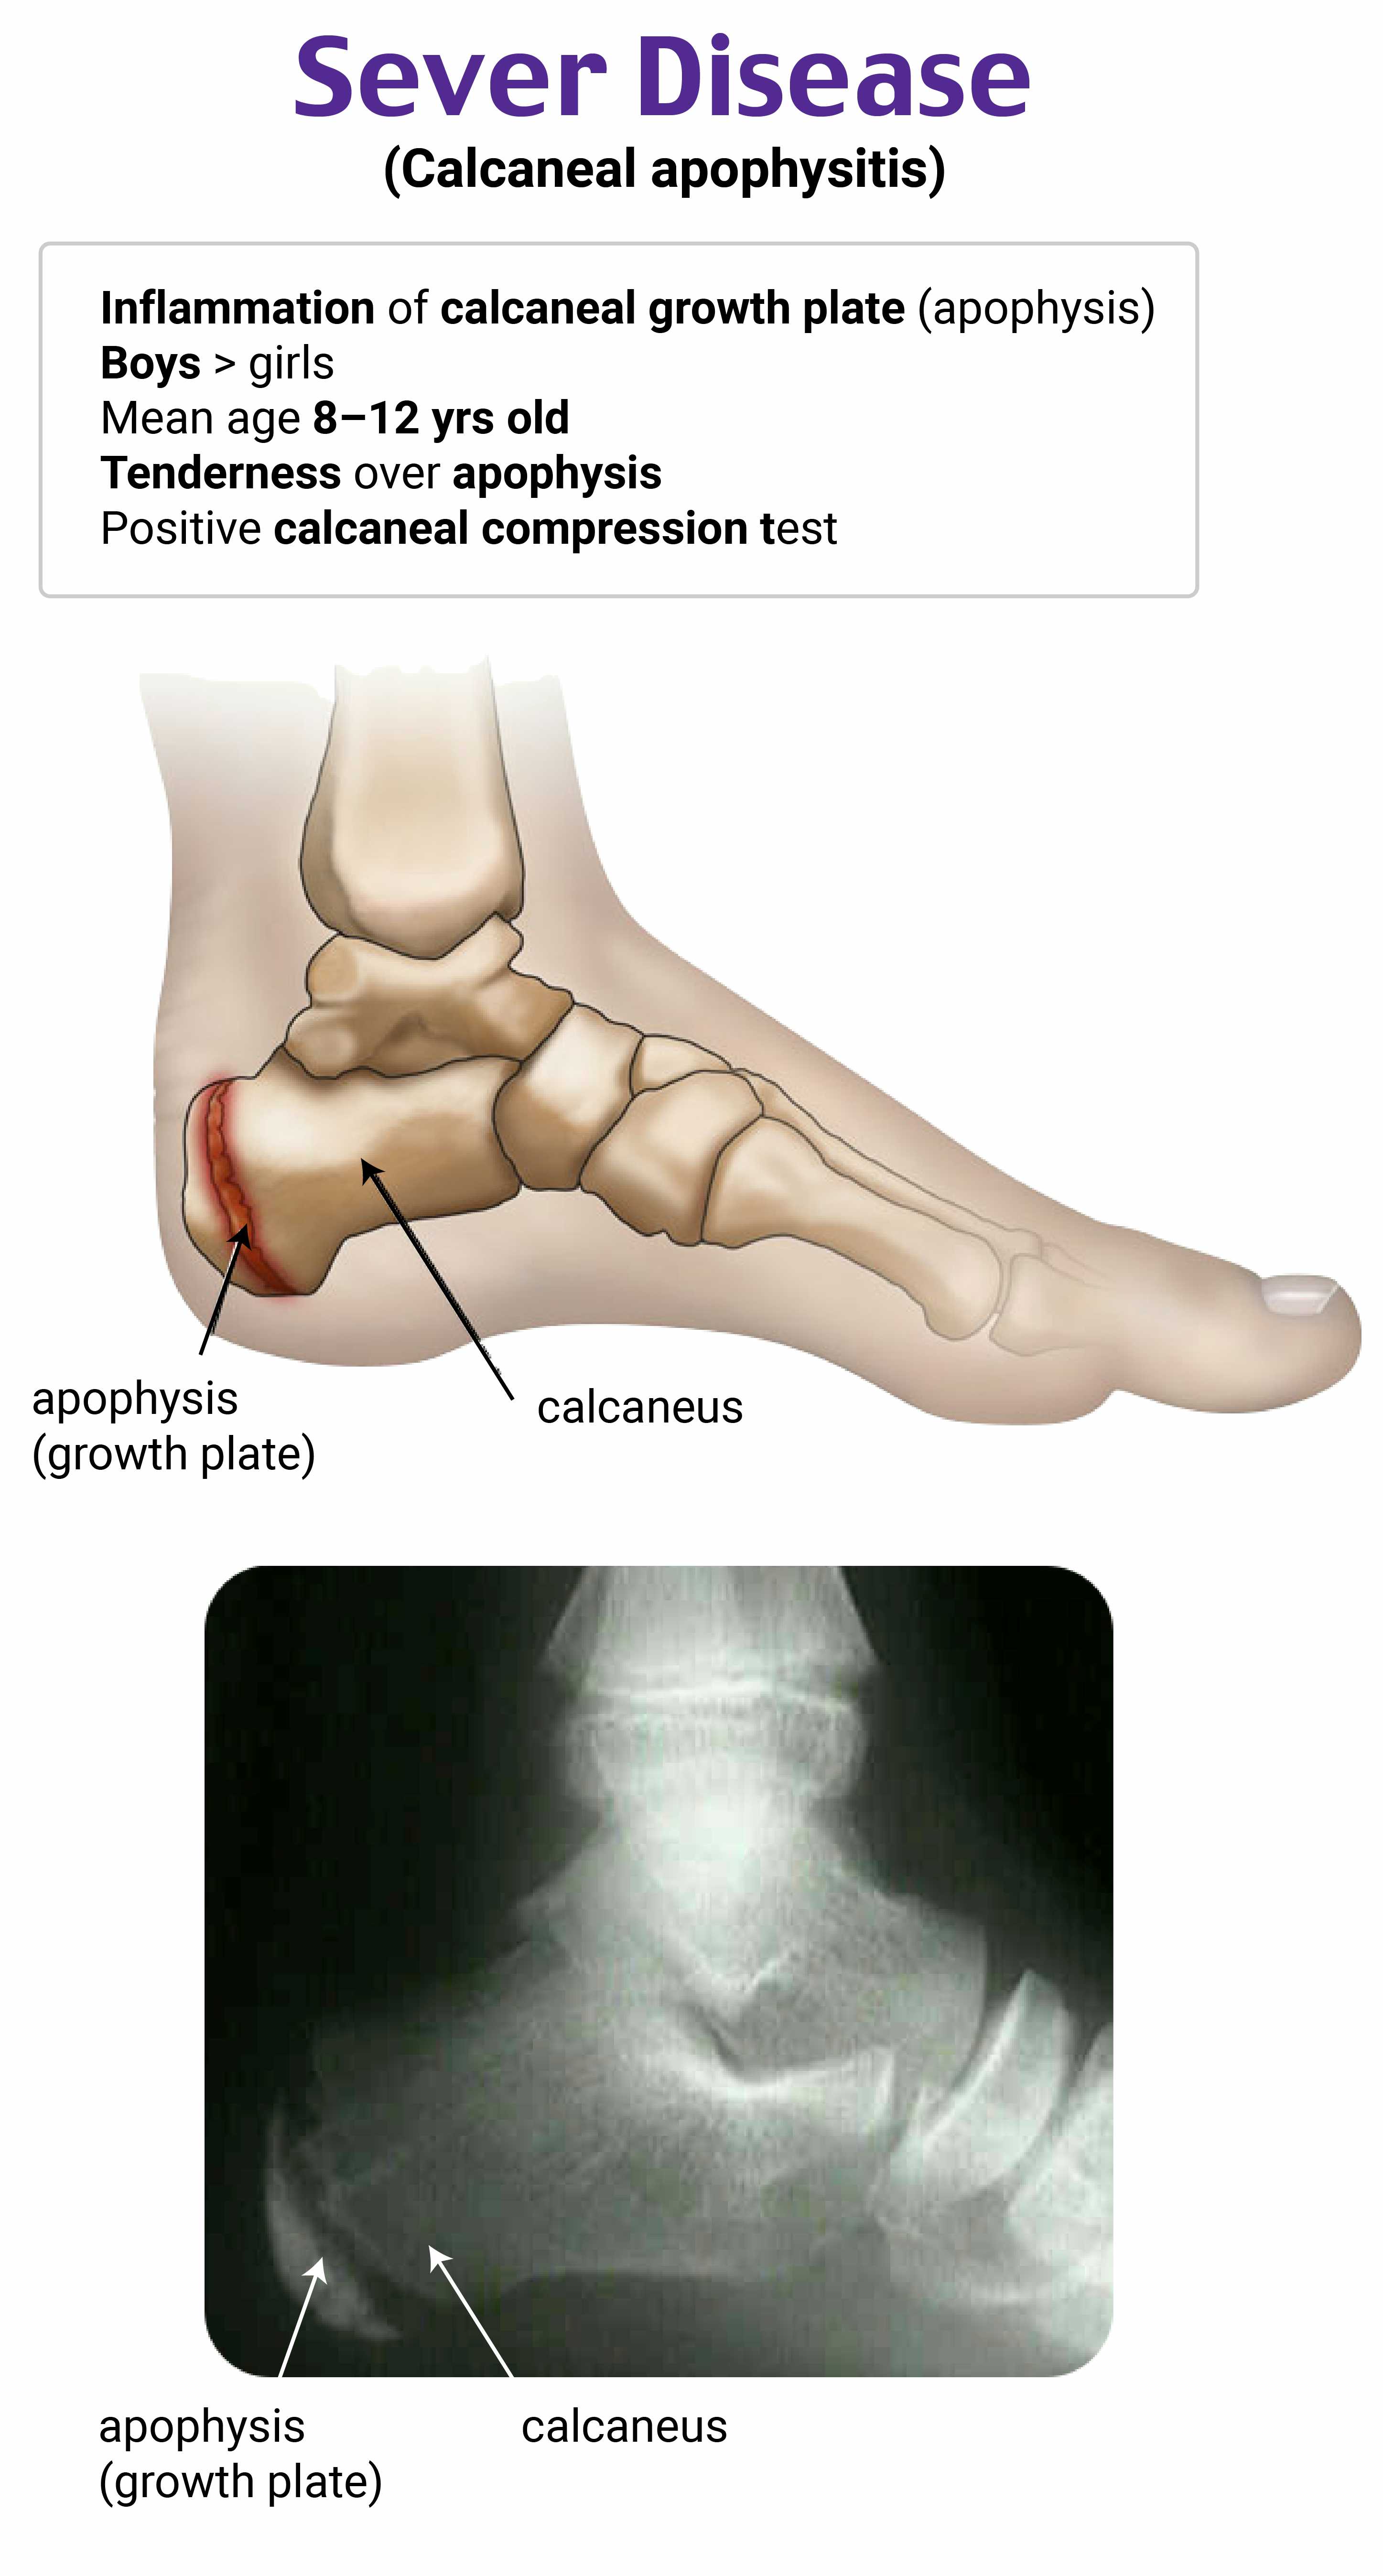

A 9-year-old boy presents to the clinic with a two-week history of bilateral heel pain. He plays soccer and basketball but denies injury to his feet. Physical examination reveals tenderness to direct palpation over the calcaneal apophysis bilaterally. No overlying erythema or warmth is noted. Which of the following is the most likely diagnosis?